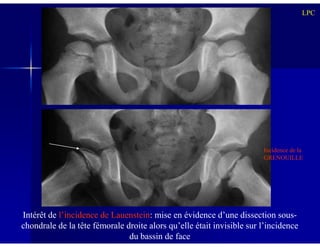

Intérêt de l’incidence de Lauenstein: mise en évidence d’une dissection sous-

chondrale de la tête fémorale droite alors qu’elle était invisible sur l’incidence

du bassin de face

Incidence de la

GRENOUILLE